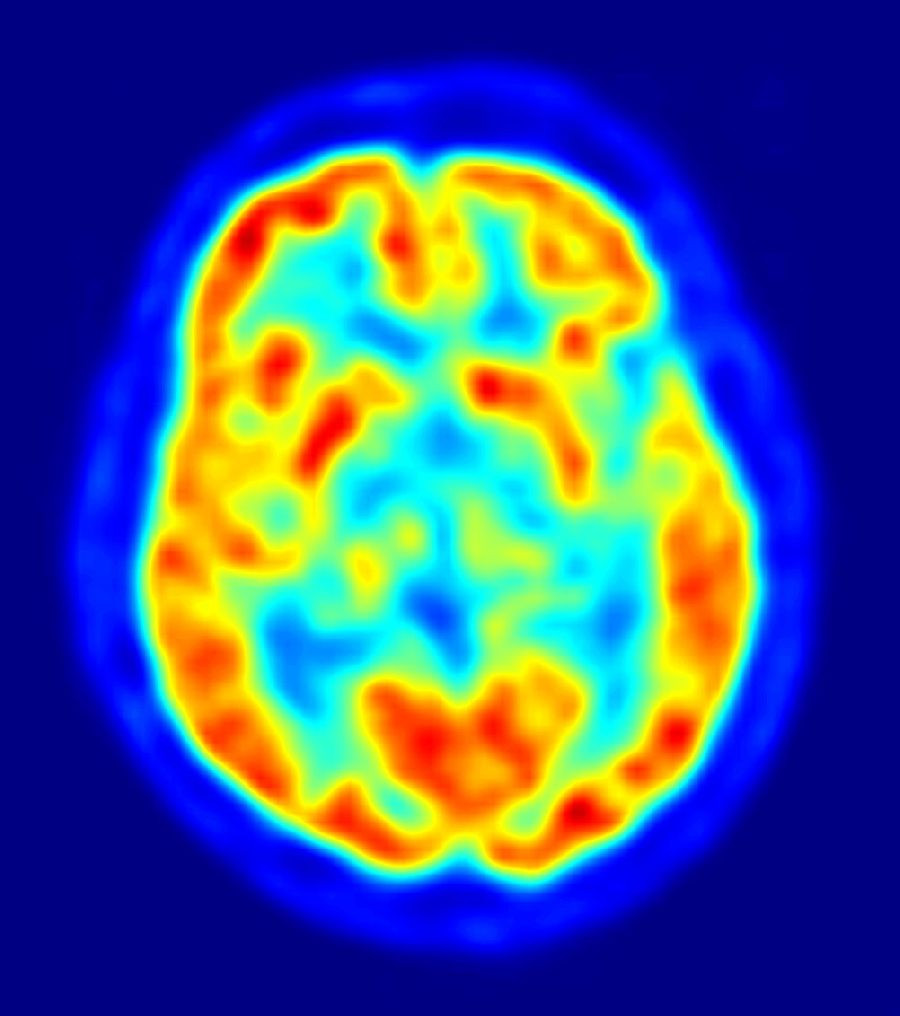

Nanomateriales de productos de consumo podrían tener impactos neurológicos al atravesar la barrera hematoencefálica

Los nanomateriales que se encuentran en productos de consumo y sanitarios pueden pasar del torrente sanguíneo al lado del cerebro en un modelo de barrera hematoencefálica con mayor o menor facilidad según su forma, creando así posibles impactos neurológicos que podrían ser tanto positivos como negativos, según revela un nuevo estudio publicado en la revista `PNAS`.

Un equipo internacional de investigadores ha descubierto que las propiedades fisicoquímicas de los nanomateriales metálicos influyen en su eficacia para penetrar en el modelo in vitro de la barrera hematoencefálica y en sus posibles niveles de toxicidad en el cerebro.

El deterioro de la integridad de la barrera hematoencefálica compromete la salud del sistema nervioso central y el aumento de la permeabilidad a las sustancias extrañas puede acabar causando daños en el cerebro (neurotoxicidad).

Estudios recientes han descubierto que los nanomateriales, como el óxido de zinc, pueden acumularse en el lado cerebral de la barrera hematoencefálica in vitro en estados alterados que pueden afectar a la actividad neurológica y a la salud del cerebro. Los nanomateriales inhalados, ingeridos y aplicados por vía dérmica pueden llegar al torrente sanguíneo y una pequeña fracción de ellos puede atravesar la barrera hematoencefálica, lo que repercute en el sistema nervioso central.